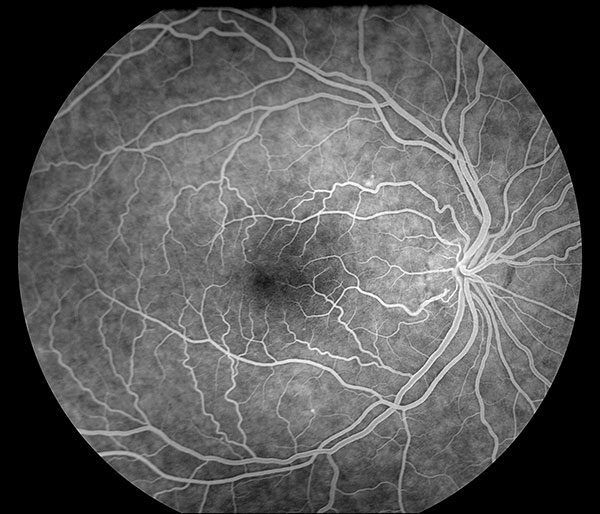

Флюоресцентная ангиограмма нормального глазного дна

Флюоресцеин поступает в глаз через 6-12 с после инъекции. Первая флюоресценция хориоидеи — слабая, неравномерная, пятнистая, т.н. пятнистое хороидальное заполнение. В течение следующих 10 с (20-25 с после инъекции) ангиограмма становится светлой, что обусловлено заполнением флюоресцеином хориокапилляров. В большинстве случаев флюоресцеин оказывается в хориоидее на 1-2 с раньше начала поступления красителя в артерии сетчатки. Заполнив ретинальные артерии, краситель следует в артериолы, капилляры, посткапиллярные венулы и, наконец, в вены. Поскольку в венах скорость тока крови в центре и пристеночно разная, заполнение вен флюоресцеином характеризуется «ламинарным током», в течение 5-10 с начальная венозная фаза переходит в развитую. В диске зрительного нерва гиперфлюоресценция начинается в начальную венозную фазу. Через 30 с после инъекции высота концентрации флюоресцеина начинает спадать. Спустя 3-5 мин после инъекции сосуды хориоидеи и сетчатки освобождаются от флюоресцеина, через 10 мин флюоресцеин полиостью вымывается из сосудистой циркуляции.

Пигментный эпителий полупрозрачен и частично экранирует свечение хориоидеи, контрастируя феномены флюоресценции сосудов прозрачной в норме сетчатки. При интенсивной пигментации рисунок сосудов сетчатки просматривается хорошо, хориоидальные сосуды плохо различимы. В случае слабой пигментации глазного дна контрастность флюоресцентных ангиограмм сильно снижается, хорошо видны сосуды хориоидеи, различимость капилляров сетчатки резко ухудшается. В макулярной области сосудистая оболочка обычно содержит повышенное количество меланина, по этой причине интенсивность свечения желтого пятна сильно ослаблена.

Фазы циркуляции красителя. В соответствии с этапами заполнения сосудистого русла сетчатки выделяется большое количество фаз исследования. В практической работе используются следующие:

- артериальная фаза — длится приблизительно с 10-й по 13-ю с от момента введения красителя, от начала до окончания прокрашивания артериол. Заполнение сосудистой оболочки (хориоидальная фаза) на 0,2-0,5 секунд предшествует по времени заполнению артерии и может иметь сегментарный характер;

- артериовенозная фаза — с 15-й по 30-ю секунду исследования, — время заполнения венул. К концу этой фазы яркость свечения артериол и венул уравнивается. Концентрация флюоресцеина в сосудах сетчатки и хориоидеи достигает максимума, апогей свечения глазного дна;

- венозная фаза — обычно начинается на 30-35-й секунде, когда венулы сетчатки начинают флюоресцировать ярче артериол. При слабой пигментации глазного дна хорошо заметны темные хориоидальные сосуды на фоне интенсивно прокрашенных сосудистой оболочки и склеры;

- поздняя венозная фаза — начинается через 1-1,5 минуты, с момента повторного уравнивания яркости свечения артериол и венул. Интенсивность флюоресценции глазного дна снижается;

- фаза рециркуляции красителя (поздняя фаза) начинается с момента, когда сосуды на диске зрительного нерва становятся темнее его поверхности (через 10-15 минут). Время начала фазы существенно зависит от характеристики светофильтров фундус-камеры. Качество получаемых фотоснимков обычно снижено вследствие крайне слабого свечения глазного дна и накопления флюоресцеина во влаге передней камеры глаза.